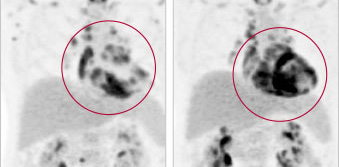

1. Making the Diagnosis: Why Cardiac Sarcoidosis Should Be on Cardiologists’ Radar

Building knowledge and awareness of an under-recognized heart condition